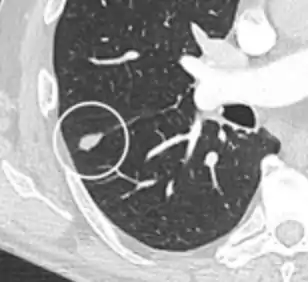

Thin slice and maximal intensity projection of a lung nodule, the latter better visualizing vascular convergence.[9]

• Vascular convergence is where vessels converge to a nodule without adjoining or contacting the edge of the nodule, and is mainly seen in peripheral subsolid lung cancers.[9] It reflects angiogenesis.[9]